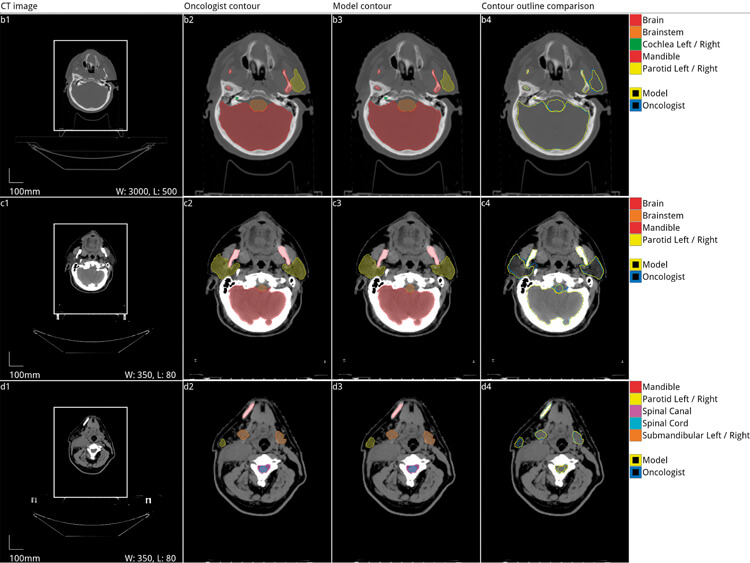

Figure 3. Automated segmentation of organs at risk of damage from radiation during radiotherapy

for head and neck cancer. Five axial slices from the scan of a 58-year-old male patient with a cancer

of the right tonsil selected from the Head-Neck Cetuximab trial dataset (patient 0522c0416) [20,21].

Adapted with permission from the original authors [13].

Convolutional neural networks have also been used in rhinology to automatically delineate critical anatomy and quantify sinus opacification [10-12]. Deep learning networks have been used in head and neck oncology to automatically segment anatomic structures to accelerate radiotherapy planning [13-18]. For laryngologists, voice analysis software will likely incorporate machine learning classifiers to identify pathology as it has been shown to perform better than traditional rule-based algorithms [19].